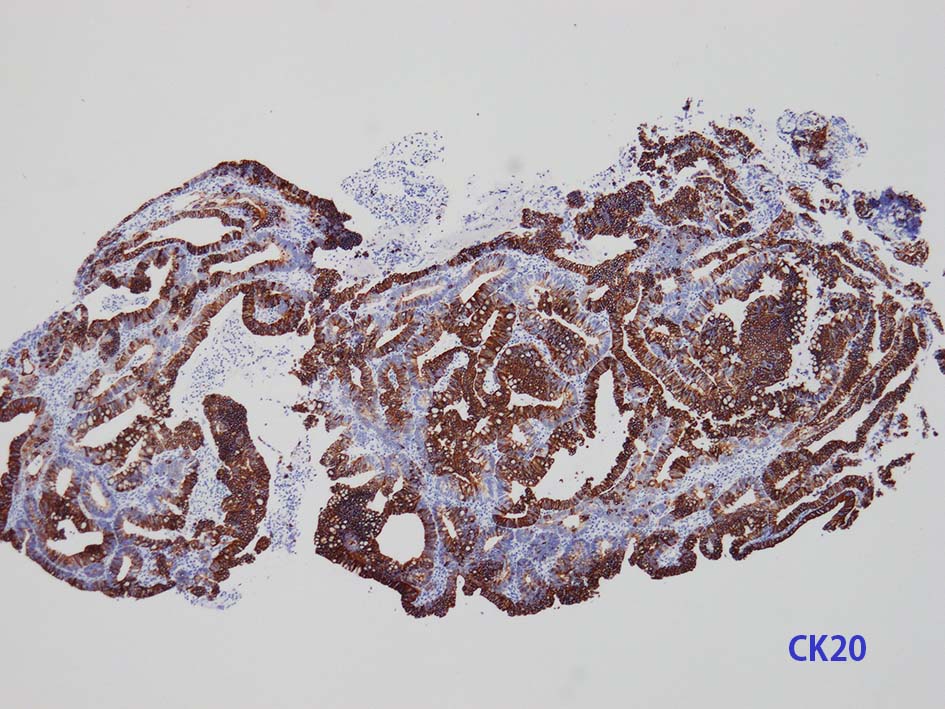

膀胱原発腺癌の診断に, サイトケラチン7および20、34βE12、トロンボモジュリン、CDX2およびβカテニンなどの免疫組織化学的パネルが提案されている。しかし他の原発部位に発生する腺癌と組織像だけでなく免疫組織化学的特徴が重複している. 原発性腺癌と転移性腺癌では予後や治療法が大きく異なるため, 鑑別診断において膀胱腺癌の診断を下す際には、臨床的、画像的、組織的、および免疫組織化学的な相関を注意深く確認する必要がある。

腸管型の腺癌。大腸の高分化腺癌と組織学的に区別は難しい.

neutrophilic exudate の付着する腸管型腺癌部分. 核はより腫大し円形、vesicularとなっている. 上記腸管型とはCK20, CK7のそまりが異なっていた. 変性のためかもしれない.